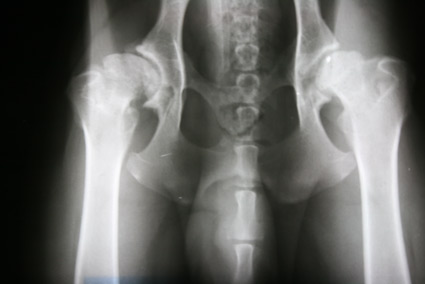

Hier nun einige HD Röntgenbilder:

HD frei / HD- A / HD-0 / HD-normal |

Normal, unauffällige Gelenke, NORBERG-Winkel von 105 Grad oder mehr |

Fast normal, geringe Veränderungen an Kopf oder Pfanne, NORBERG-Winkel von mindestens 100 Grad |

Leichte Inkongruenz, divergierender Gelenkspalt, NORBERG-Winkel um 100 Grad |

Gravierende Veränderungen mit arthrotischen Zubildungen, NORBERG-Winkel zwischen 90 und 100 Grad |

Das gesamte Gelenk ist stark verändert, evtl. eine vollständige Luxierung, NORBERG-Winkel unter 90 Grad |